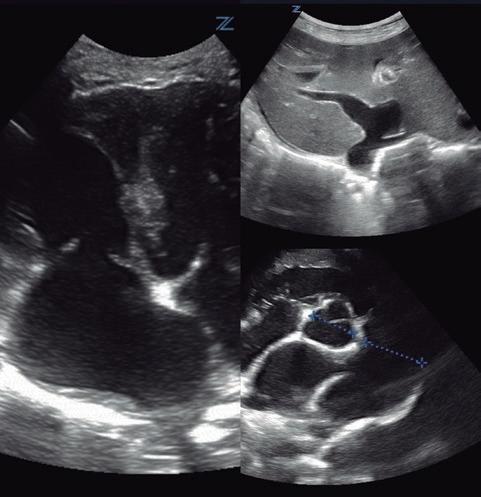

Bloqueantes de canales del calcio Hidralazina, nitratos e IECA